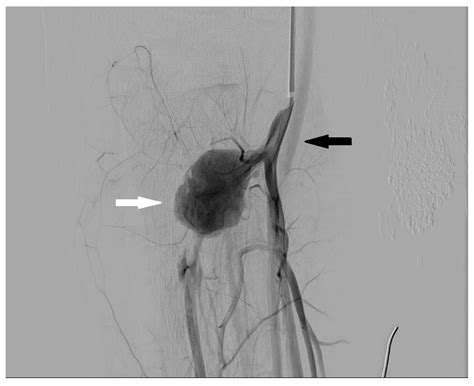

At its core, Digital Subtraction Angiography is a fluoroscopic technique that uses a computer-aided process to subtract the background image from a subsequent image taken after the injection of a contrast agent. The process begins with a "mask" image, which captures the anatomy of the target area without any contrast. Once the radiopaque contrast dye is injected into the bloodstream, a second set of images is captured. The computer then mathematically subtracts the mask from the contrast-filled images, leaving only the opacified vessels visible on the screen.

This process effectively removes visual "noise," allowing interventional radiologists to see even the smallest branches of an artery. Because of its superior contrast sensitivity and spatial resolution, it remains the preferred method for assessing conditions like aneurysms, stenosis, and arteriovenous malformations.

• Tumor Embolization: Helps surgeons navigate to the precise blood supply feeding a tumor, allowing for targeted treatment.